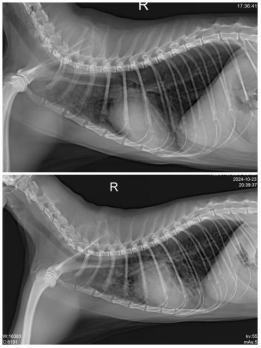

首先,我们进行了胸部X光检查,发现肺部出现弥漫性密度增高的现象,这可能是肺部积水的信号,也提示可能存在心脏问题。此外,X光片还显示了支气管征象,心脏轮廓不清晰,暗示着心脏可能存在增大或其他异常情况。